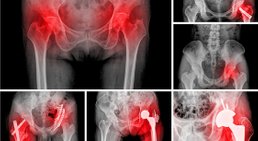

Hüftprothese

Eine Hüftprothese ersetzt ein geschädigtes Hüftgelenk. Neben Knieprothesen zählen Hüftprothesen zu den am häufigsten implantierten Prothesen im Bereich der...

Hüfte: Hüftarthrose, Fehlstellungen, Hüftkopfnekrose, Einklemmungsschmerzen im Leistenbereich, kindliche Hüfte; Operationen: Hüftotalendoprothese, Impingementoperation